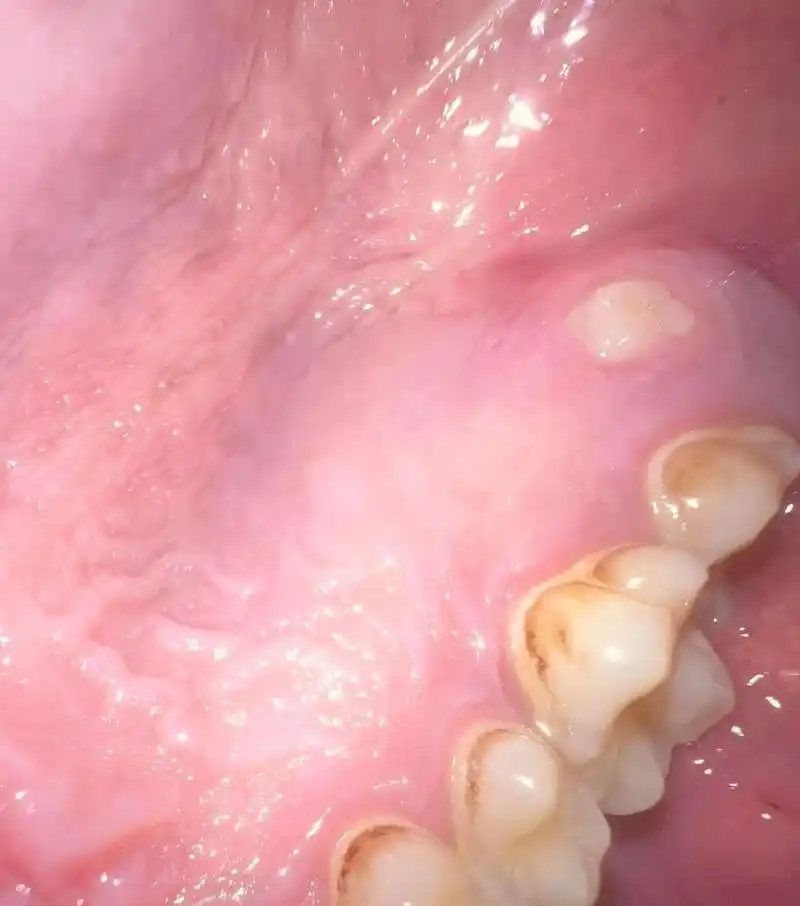

我怎么牙龈这个位置长了个牙齿啊?